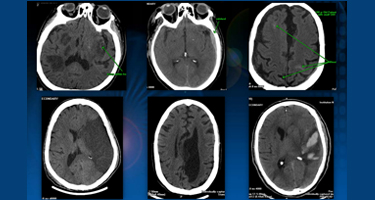

This prospective study evaluates feasibility, accuracy, and safety of portable CT scanninng in an initial series of 85 surgeries. Pavel Barsa, Robert Frőhlich, Vladimír Beneš III, & Petr Suchomel (2014). Acta Neurochir (156) 1807–1812.